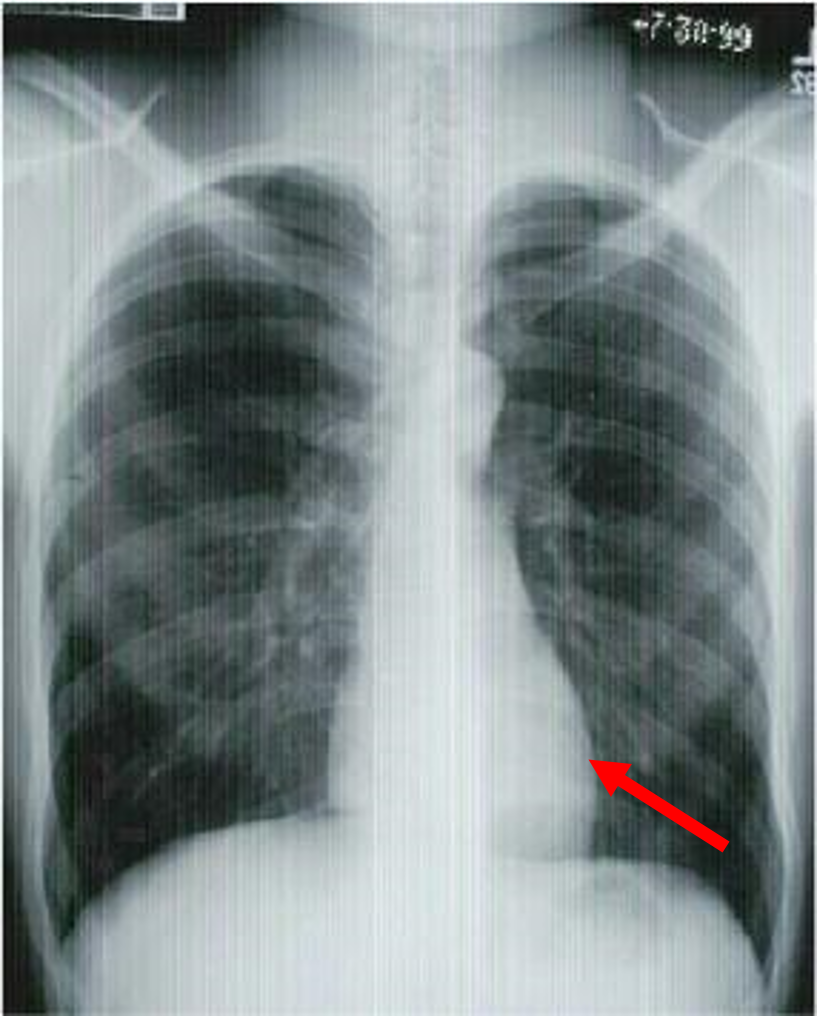

three rules of a lateral chest x ray

diaphragm shadow

retrosternal space

retrocardiac space

lateral chest